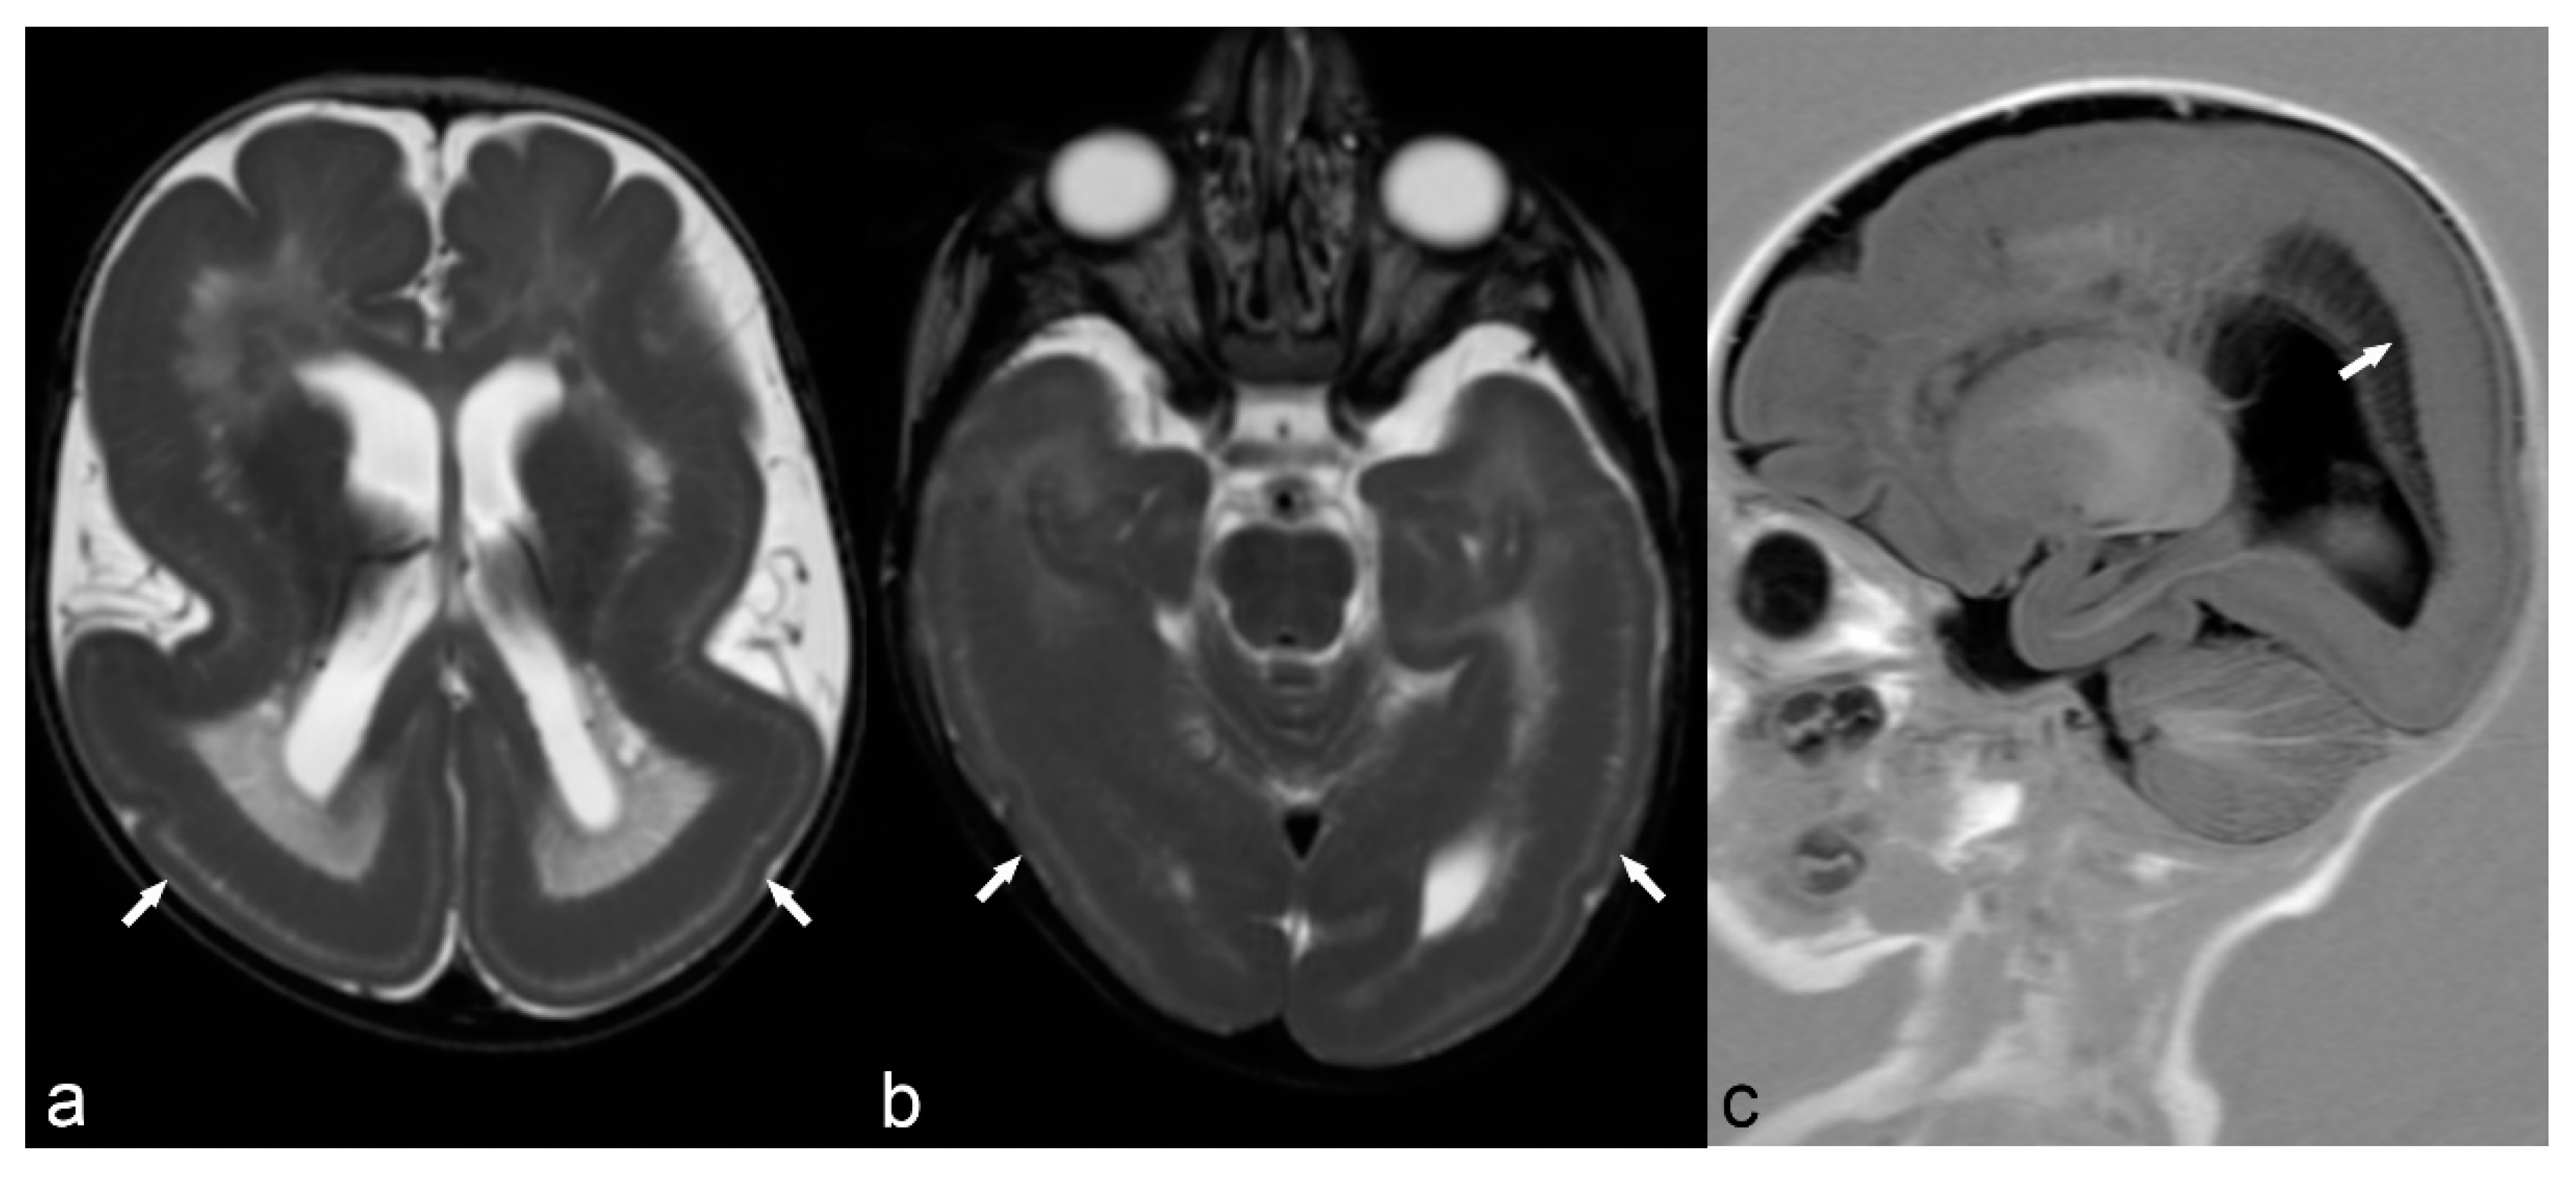

Classical lissencephaly is characterized by reduced or absent gyri associated with a thickened cortex and shallow sulci. Microscopically, the cortex lacks the normal lamination and consists of only 4 layers instead of the typical 6 layers. Macroscopically, the sylvian and Rolandic fissures are poorly developed and there is a failure of operculization of the insular areas [85]. This results in a smooth appearance of the brain surface with the characteristic “Figure 8” or “hourglass” shape of the brain in axial images (Figure 6) [83]. There are several gene mutations implicated in its pathogenesis and a wide spectrum of clinical manifestations such as severe intellectual disability, hypotonia and epilepsy. It is usually diagnosed early in life, although mild cases may have delayed presentation [69]. Miller-Dieker syndrome (MDS) is a severe form of classical lissencephaly associated with facial dysmorphism and occasionally other congenital abnormalities, epilepsy and a severely shortened life expectancy, related to a chromosome 17 gene deletion. Cobblestone lissencephaly is a distinct form of lissencephaly characterized by a nodular appearance of the brain cortex secondary to abnormal organization of the cortical layers.

Figure 6.

6-month-old baby. Axial T2WI slices through the lateral ventricles (a) and occipital lobes (b) demonstrate a distinct lack of normal brain gyration with a smooth and thickened appearance of the cortex and unfolded gyri, most pronounced in both parietal, temporal and occipital lobes (arrows) consistent with lissencephaly. Note the posterior-anterior gradient with some rudimental sulcation seen in the frontal lobes. Band heterotopia can be clearly seen in the parietal regions on sagittal T1 IR (c) with cobblestone appearance (arrow).